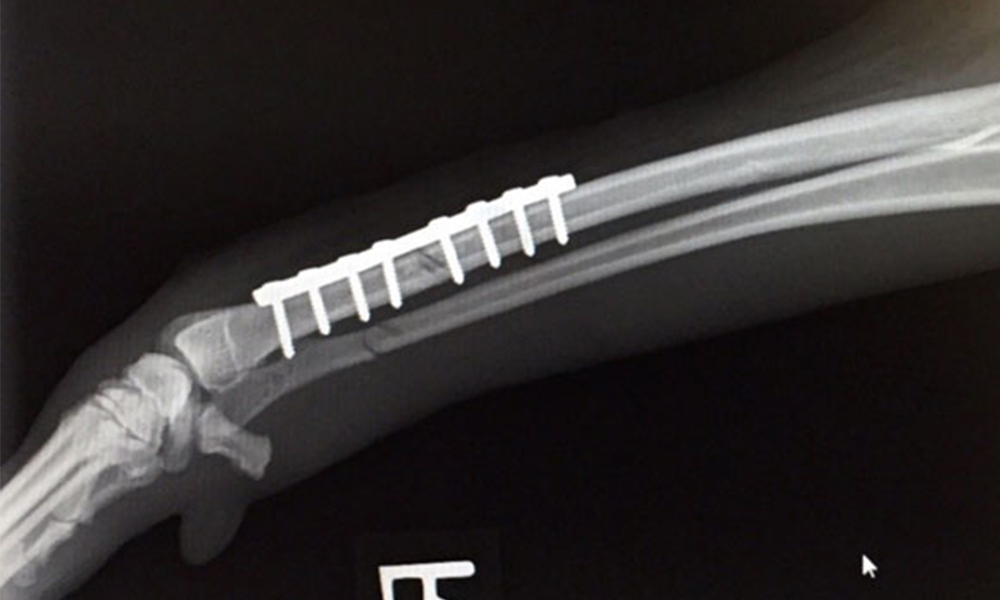

Italian Greyhound puppies in particular are incredibly lively and care needs to be taken to ensure they don’t damage their limbs. Having long slim legs, compared to their body mass and their desire to run and jump can make them more vulnerable to leg fractures. Adults too can have accidents, which result in leg fractures.